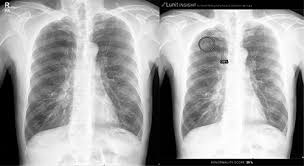

- 흉부 X‑선 또는 흉부 CT로 발견

- 이전 영상과 비교하여 결절의 변화 여부 확인

- 결절 크기·형태·경계·석회화 여부 등 특징 분석